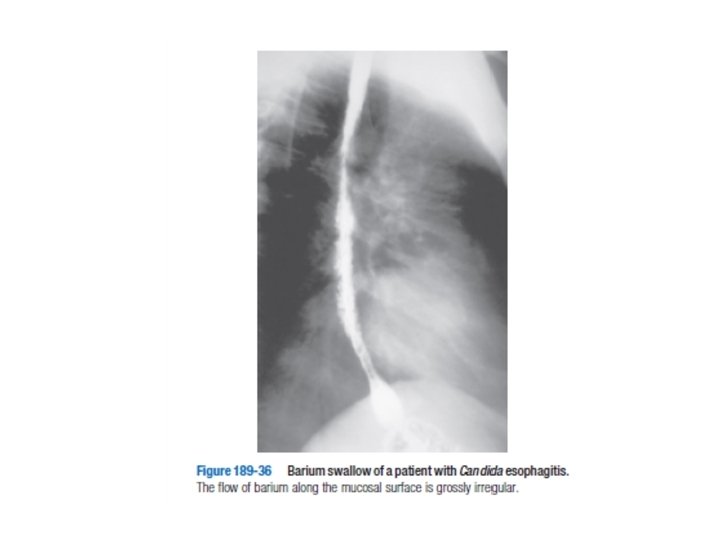

GASTROİNTESTİNAL KOMP. Özefagus lezyonları; • Kandida, HSV, CMV enfeksiyonları – Disfaji, odinofaji, kilo kaybı • Özefagial kandida; oral kandidası olup CD 4 sayısı 100’ün altına düşenlerde olur • Tanı klinik ile konup oral flukonazol yada ketokonazol başlanabilir • Dirençli olgular endoskopik biopsi ile değerlendirilmelidir